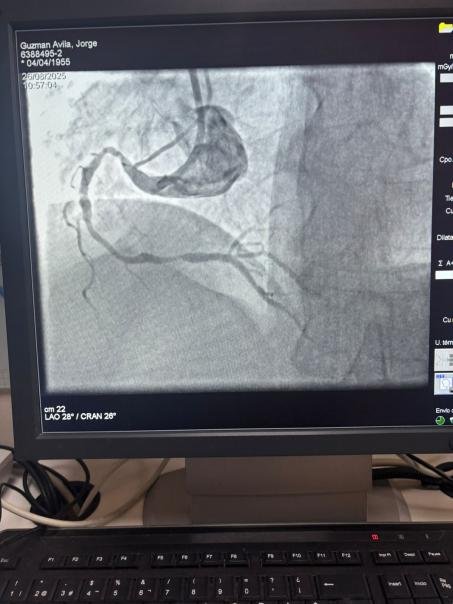

Estamos orgulhosos de compartilhar um caso notável do Hospital Sótero del Río, Chile, onde o Dr. Martín Valdebenito tratou com sucesso uma lesão fortemente calcificada na artéria coronária direita (primeira curva) usando nosso Sistema de Cateter de Dilatação Coronária Vesscrack.

O procedimento alcançou excelentes resultados, com a região calcificada efetivamente rachada e o fluxo do vaso restaurado. Isso marca outro marco na expansão do acesso global a soluções avançadas para calcificação coronariana complexa.

A comparação entre as imagens angiográficas pré-procedimento e pós-procedimento demonstra claramente o impacto clínico significativo de nossa tecnologia IVL.